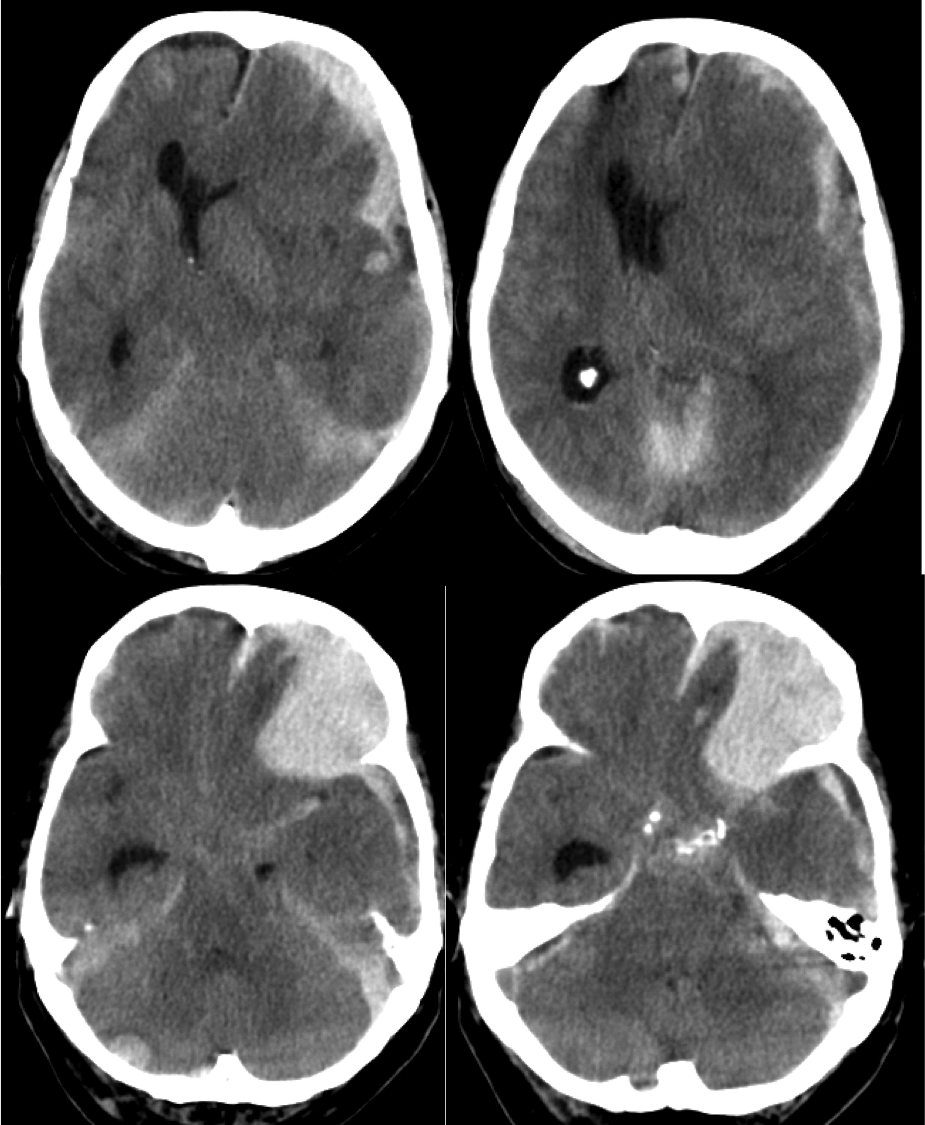

Hematoma Epidural.

- Frecuente en adultos jóvenes. Niños y ancianos es poco frecuente.

- Lente biconvexa hiperdensa. Si hay foco hipodensos en su interior puede indicar sangrado activo = signo del remolino = actitud quirúrgica.

- Normalmente limitada por suturas. Pueden cruzar la hoz y el tentorio

- Se localiza entre la duramadre y la tabla interna del cráneo.

- Suele ocurrir en el sitio de impacto por golpe directo que produce desgarro de vasos meníngeos arteriales y venosos.

- La arteria meníngea media es la más afectada y causa el hematoma temporo parietal.

- Los sangrados venosos mas frecuente es el debido a la afectación del seno esfenoparietal por fractura del ala mayor del esfenoides. También puede ser debido a afectación de los senos transversos y sigmoides en la fosa posterior.

- Se puede asociar con HSD por contragolpe, contusiones intracraneales y efecto masa.